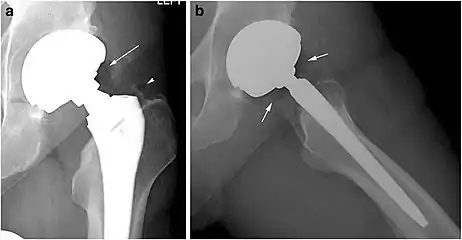

Pneumarthrosis is the presence of air in a joint. Its presentation on radiography is a radiolucent cleft often called a vacuum phenomenon, or vacuum sign.[7] Pneumarthrosis is associated with osteoarthritis and spondylosis.[8]

Pneumarthrosis is a common normal finding in shoulders[7] as well as in sternoclavicular joints.[9] It is believed to be a cause of the sounds of joint cracking.[8] It is also a common normal post-operative finding at least after spinal surgery.[10] Pneumarthrosis is extremely rare in conjunction with fluid or pus in a joint, and its presence can therefore practically exclude infection.[8]

X-ray of a hip with hip replacement and pneumarthrosis, in this case aseptic.